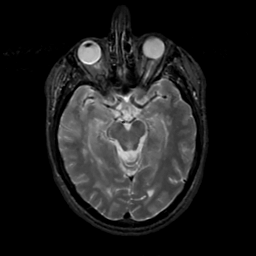

MR Study #3, February 24, 1991 -- Slice #20